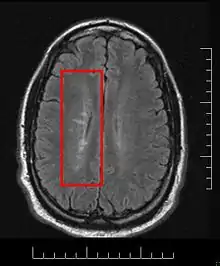

Multiple sclerosis is considered a disease of the white matter because normally lesions appear in this area, but it is also possible to find some of them in the grey matter.[30]

Using high field MRI system, with several variants several areas show lesions, and can be spacially classified in infratentorial, callosal, juxtacortical, periventricular, and other white matter areas.[31] Other authors simplify this in three regions: intracortical, mixed gray-white matter, and juxtacortical.[32] Others classify them as hippocampal, cortical, and WM lesions,[33] and finally, others give seven areas: intracortical, mixed white matter-gray matter, juxtacortical, deep gray matter, periventricular white matter, deep white matter, and infratentorial lesions.[34] The distribution of the lesions could be linked to the clinical evolution[35]

Due to the distribution of the lesions, since 1916 they are also known as Dawson's fingers.[40] They appear around the brain blood vessels.

Lesions under MRI

Most MS lesions are isointense to white matter (they appear bright) on T1-weighted MRI, but some are "hypointense" (lower intensity). These are called "black holes" (BH). They appear specially in the supratentorial region of the brain.

When BH's appear, around half of them revert in a month. This is considered a sign of remyelination. When they remain, this is regarded as a sign of permanent demyelination and axonal loss. This has been shown on post-mortem autopsies.[96]

Small lesions are invisible under MRI. Therefore, clinically assisted diagnostic criteria are still required for a more accurate MS diagnosis than MRI alone.[97]

The lesion evolution under MRI has been reported to begin as a pattern of central hyperintensity. This was seen in the majority of new lesions, both on proton density and contrast-enhanced T1-weighted images.[98] When gadolinium is used, the lesion expansion can be classified as nodular or ringlike[99]

Lesion evolution can be followed via MRI[103]